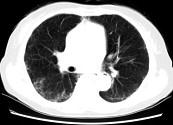

问题 女,35岁,咳嗽,咳痰,发热3月余,胸部CT如图,最可能的诊断为 ( )

选项 A.类风湿肺炎 B.红斑狼疮性肺炎 C.间质性肺炎 D.肺结节病 E.肺部感染

答案 C